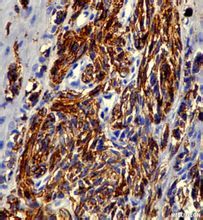

抗體抗獨特型抗體疫苗是免疫調節網路學說發展到新階段的產物。網路學說認為,生物體對抗原的免疫答應是通過獨特型(ID)與抗獨特型(Anti-Id)之間的反應而調節的。獨特型是指與某一抗原免疫

應答有關的,能與抗原發生特異性反應的一組細胞(T、B細胞克隆)及其因子(T細胞因子和抗體)所具有的抗原特異性,在正常情況下,機體的Id處於極低水平,當機體受到抗原刺激時,T、B淋巴細胞增殖、抗體水平升高,相應的Id水平也升高,繼而刺激Anti-Id(Ab2)的產生,Anti-Id的產生又可刺激Anti-anti-Id(Ab)的產生。如此循環下去,構成對原始應答的複雜免疫調節網路。當抗原與Ab1結合後,可以阻礙Ab2與Ab1上的Id結合 ,因而說明Ab2能識別Ab1的抗原結合部位。Ab2β模擬抗原,可刺激機體產生與Ab1具有同等免疫效應的Ab3由此製成的疫苗稱為抗獨特型疫苗或內影像疫苗。抗獨特型疫苗不僅能誘導體液免疫,亦能誘導細胞免疫,並不受MHC的限制,而且具有廣譜性,即對易發生抗原性漂變的病原能提供良好的保護力(見圖23-2)。 單抗技術以及“獨特型網路”的發現意味著Ig可被用作“替代”抗原。對糖類和脂類抗原來說,這一方法可以製造一個“蛋白質拷貝”,而蛋白質作為疫苗具有某些優點。